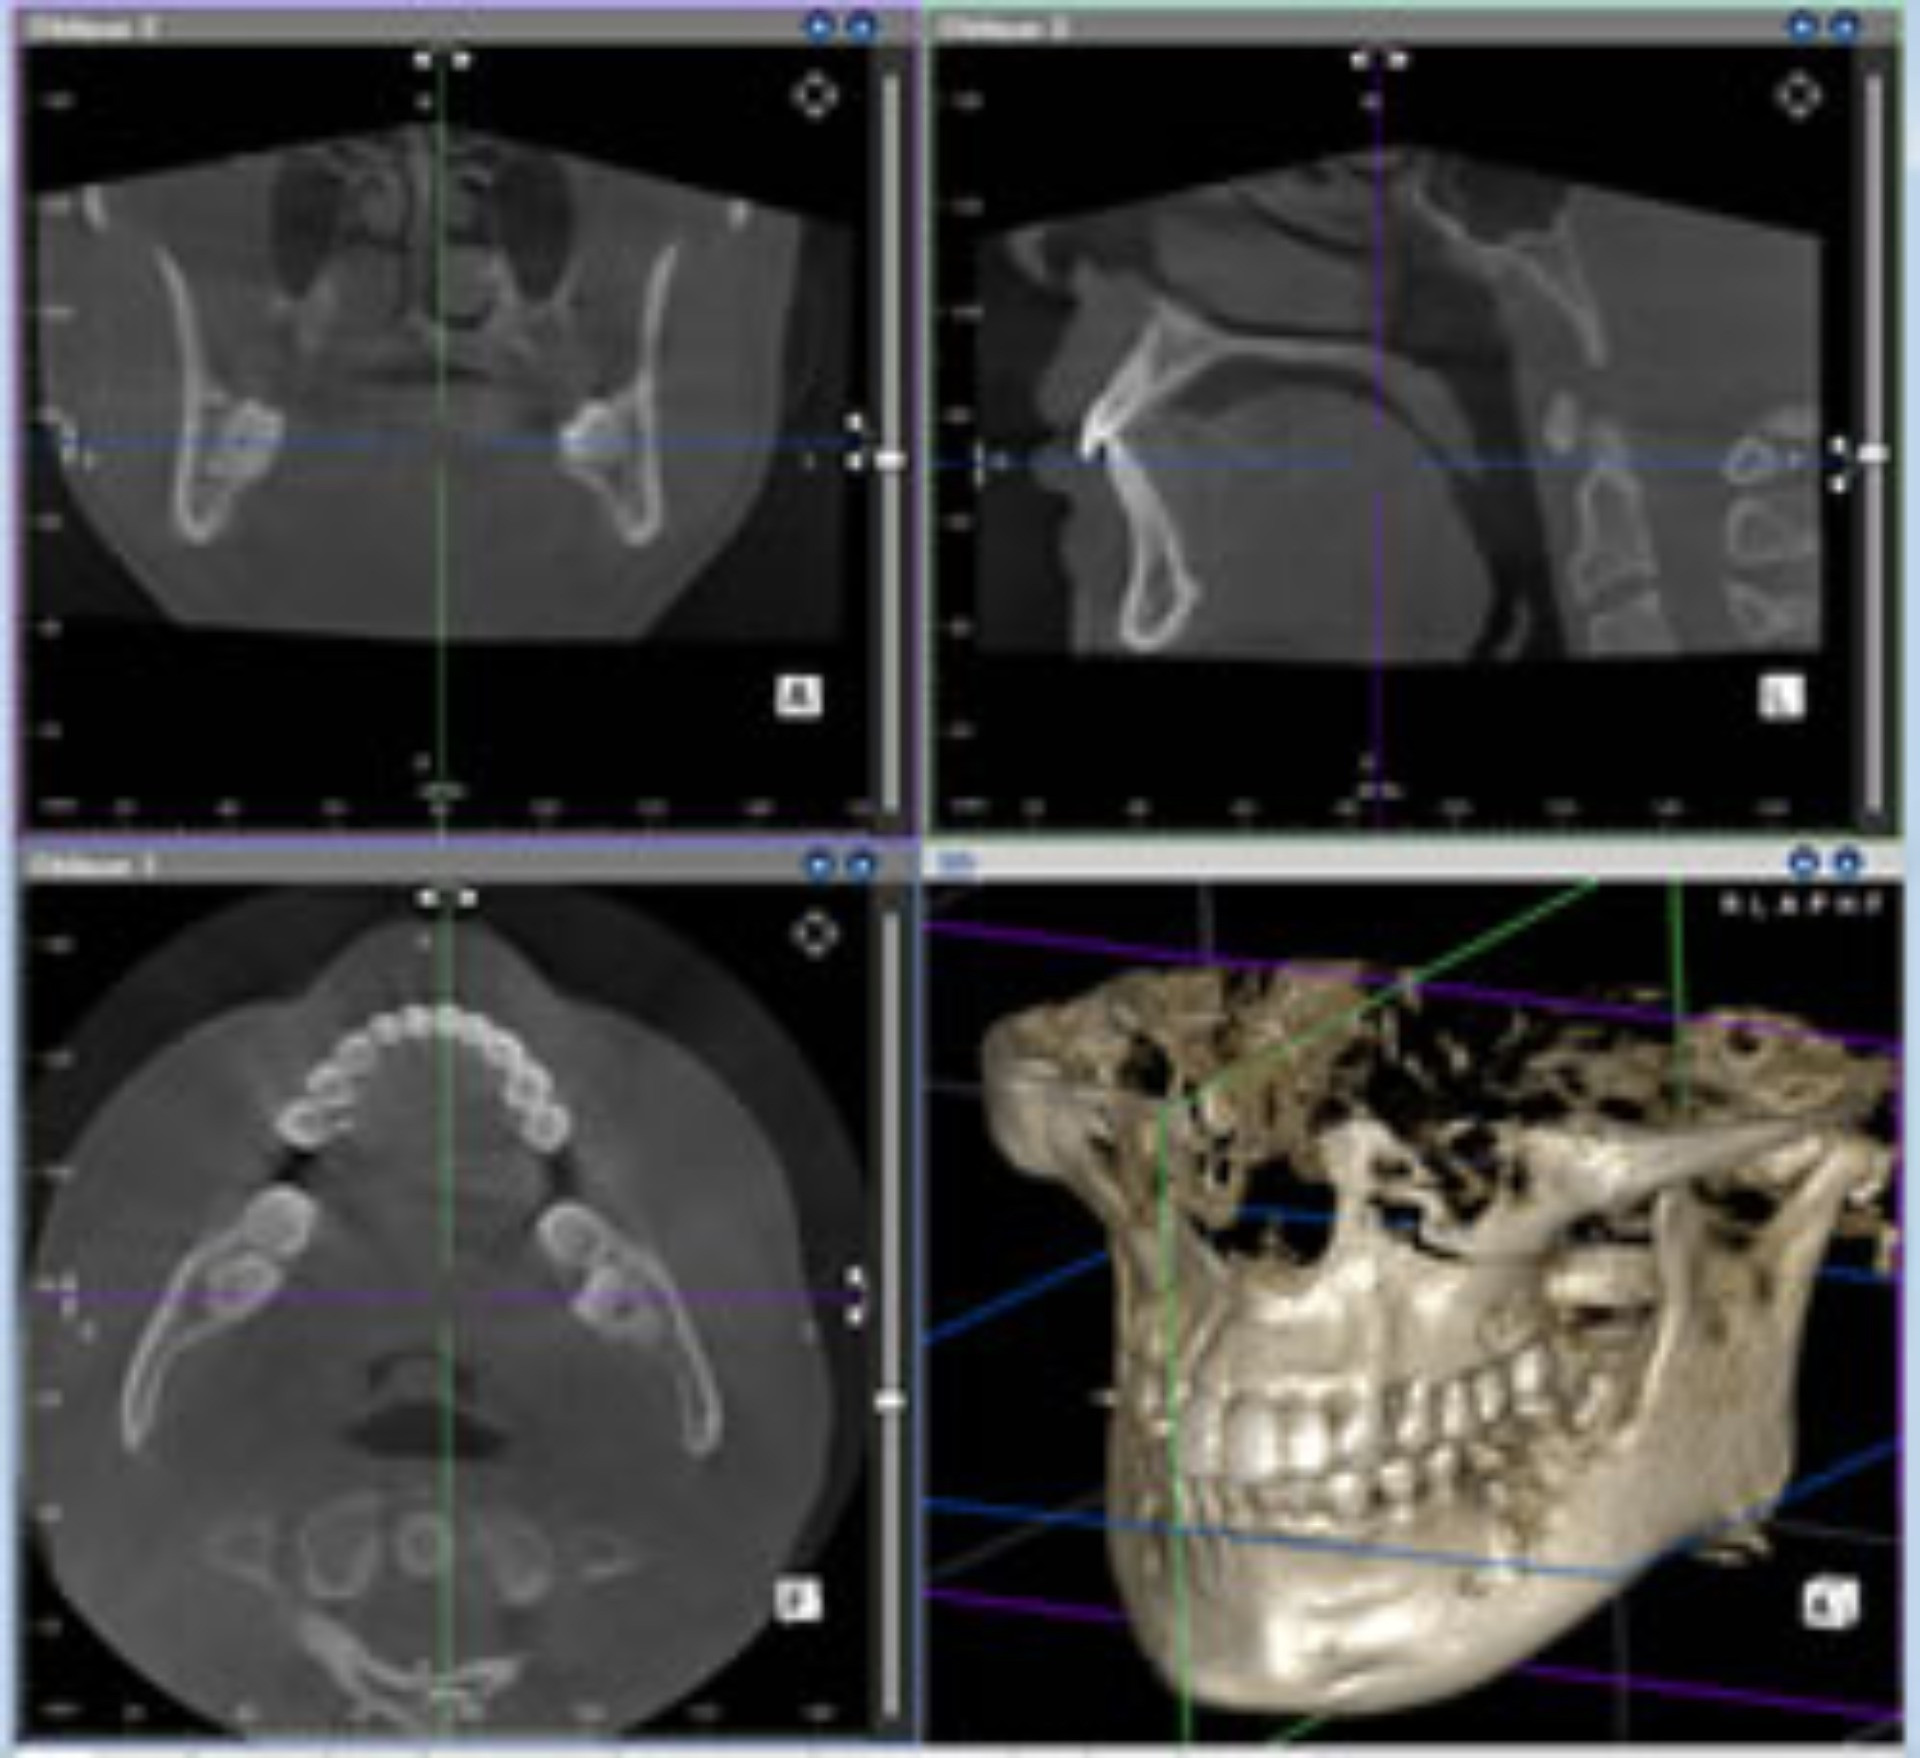

従来のレントゲン画像は平面像(二次元)でしたが、歯科用CT画像は立体画像(三次元)で表現することが可能ですので、歯周病の現状や歯の根の形態、歯の周りの骨の状態など、お口の中をより細部まで、正確に診断することができます。画像は、歯科用ユニットに備え付けられたモニターに映し出し、ご確認いただけます。

CT画像からは、従来のレントゲンでは見えなかった顎の骨の立体的な形態や、神経の位置把握、さらに骨密度の診査にも利用できます。 |

インプラント治療の成功のカギとなる骨の量・骨の密度がCTにより正確に算出されることで治療の成功率は飛躍的に向上します。

またインプラントの埋入量や方向なども的確にシミュレートされるので、CT撮影なしで行う手術に比べ安全性も格段に向上します。

CT撮影では三次元的に骨のない場所が画面上で一目で分かるためプローブの入らない場所でも正確に病巣を見つけることができます。

根の本数や神経の入っている管の方向、そして位置を正確に把握することができます。

CT画像では、埋まった歯や周囲の歯、神経や血管の位置関係を容易に確認することができます。